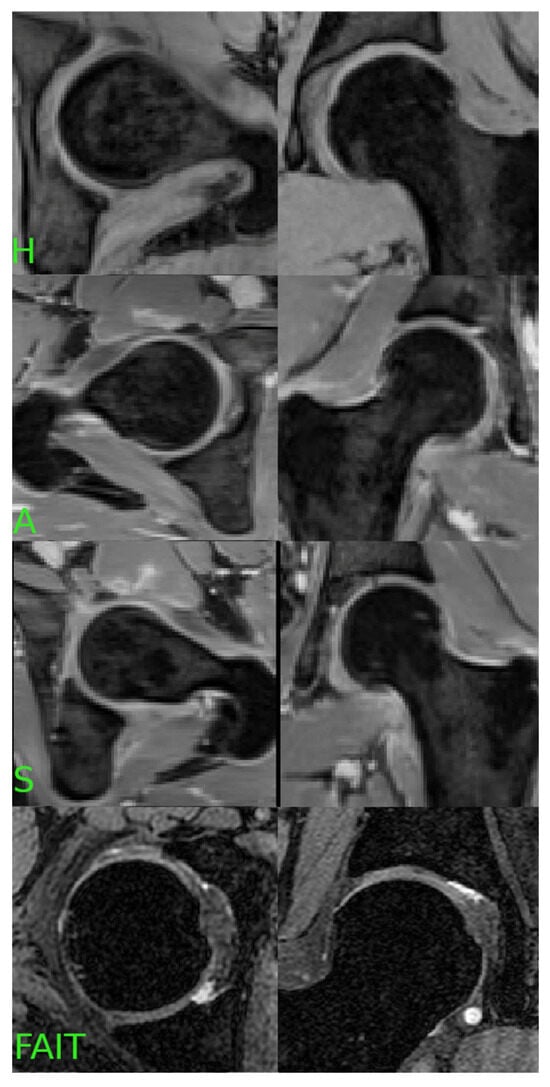

2.3. Dataset Preparation

In Cohorts 1 and 2, water-only images and the associated segmentations were separated into left and right hip regions for each subject. For patients in Cohort 1 with unilateral symptoms, the clinically affected hip was labeled as “S” (symptomatic), while the contralateral hip—confirmed to be pain-free and lacking morphological features of impingement—was labeled as “A” (asymptomatic). Importantly, we did not assume bilateral symmetry of FAI; rather, each hip was independently evaluated based on clinical records and imaging review by a musculoskeletal radiologist.

For Cohort 2, which included healthy volunteers, both hips were labeled as “H” (healthy) based on the absence of symptoms and imaging findings suggestive of FAI.

For Cohort 3, only the symptomatic side was available per subject. All 185 cases were thus labeled as “S”, representing confirmed symptomatic FAI based on the clinical criteria defined in the FAIT study [19].

Using this schema, we constructed a training dataset of 82 hips from Cohorts 1 and 2 (20 H, 31 A, 31 S) and an external validation dataset of 185 symptomatic hips (S) from Cohort 3.

Figure 2. The dataset was labeled according to the presence of hip pain: “H” for healthy hips, “A” for asymptomatic FAI, “S” for symptomatic FAI and the Cohort 3 (FAIT) dataset. This labeling scheme enabled the classification of hip conditions based on radiomic features extracted from the segmented ROIs.